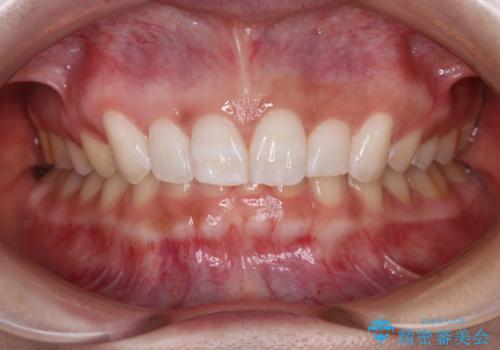

[ 総合歯科診療 ] がたつきの改善とセラミック治療

![[ 総合歯科診療 ] がたつきの改善とセラミック治療の症例 治療前](https://seimitsushinbi.jp/wp/wp-content/uploads/2024/03/f0f438a14c56b185411649f48b5b188c-500x350.jpg?v=1710833163)

![[ 総合歯科診療 ] がたつきの改善とセラミック治療の症例 治療後](https://seimitsushinbi.jp/wp/wp-content/uploads/2024/03/7212917eb9c4ef33050c52e7f9724490-500x350.jpg?v=1710833188)